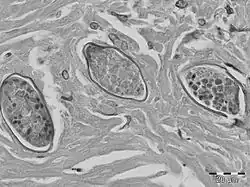

S. malayensis eggs have been found in liver granulomas, embedded within dense, fibrous tissue. The eggs of S. malayensis have a thin-walled, yellowish shell. The eggs contain miracidia and are approximately 50 μm long × 28 μm wide. The ova is not operculated and has no bipolar plugs and the thin covering was not striated.[6]